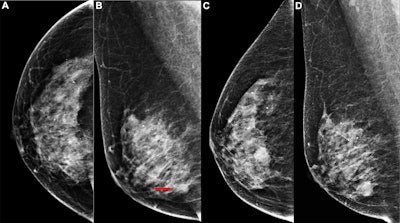

Images depict the right breast in a 63-year-old woman with interval breast cancer. (A, B) Screening mammograms in the (A) craniocaudal and (B) mediolateral oblique views show a right breast asymmetry (arrow) initially interpreted as normal tissue (BI-RADS category 2). (C, D) Diagnostic mammograms 17 months later in the (C) craniocaudal and (D) mediolateral oblique views reveal a high-density oval mass with indistinct margins. Ultrasound examination (not shown) demonstrated a 15.9 × 11.2 × 9.6 mm irregular hypoechoic mass, which was confirmed at biopsy to be invasive ductal carcinoma grade I.RSNA